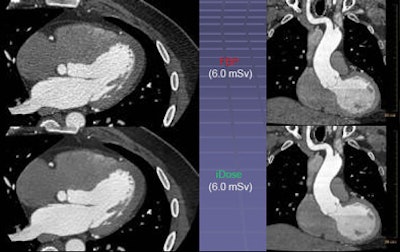

In contrast, the iDose algorithm (Philips Healthcare, Andover, MA) that Mendel described in his ISCT talk uses an iterative method designed to reproduce the look of full-dose filtered back projection (FBP) at a much lower dose using an iterative method. The goal is to allow use of a higher percentage of iterative reconstruction while maintaining a clinically acceptable image.

First, the projection data itself are denoised with the application of a Poisson denoising algorithm. Then in the pixel space, iDose compares the image to a noiseless ideal anatomical model, enabling noise reduction with an appearance that is very similar to the full-dose image and does not shift the noise spectrum significantly, Mendel said.

"So even at 80% dose reduction, the images are virtually identical" to a full-dose image, even when the images are rendered, he said. In contrast, the first-generation systems show major shifts in the noise spectrum, sharpening edges and blurring other structures compared to standard images.

The key aspect of iDose is that it maintains the noise power spectrum (thus the appearance) of a full-dose image while utilizing high levels of dose reduction, Mendel said.